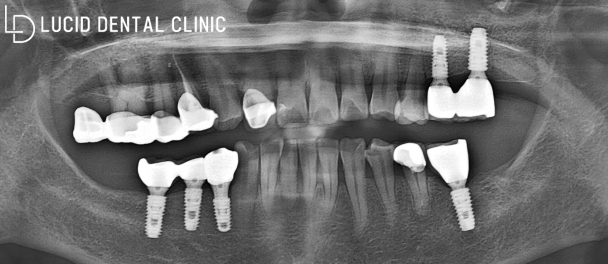

- 임플란트 수술 후

저는 임플란트 수술 과정을

서초동 치과 가 제작해 드린

지르코니아 보철 수복과 함께

마무리 작업(교합 조정, 연마 작업)

또한 문제없이 마무리하였습니다.

제가 기대하던 결과 그대로 나와

환자께서도 크게 만족해하셨는데요